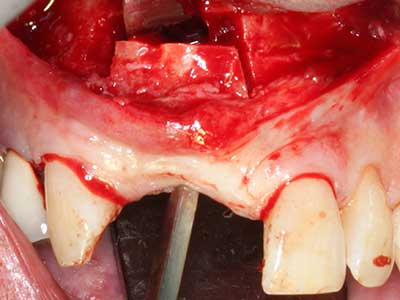

Fig. 2: Vertical and horizontal lateral maxillary defect with a high smile line with indication for pre-implant reconstruction.

Fig. 13: Adequate irrigation with the 4-mm residual bone width is essential for this 52-year-old patient during the bone splitting.

Fig. 14: Placement of four tapered RSX implants (Bego Implant Systems, Bremen).